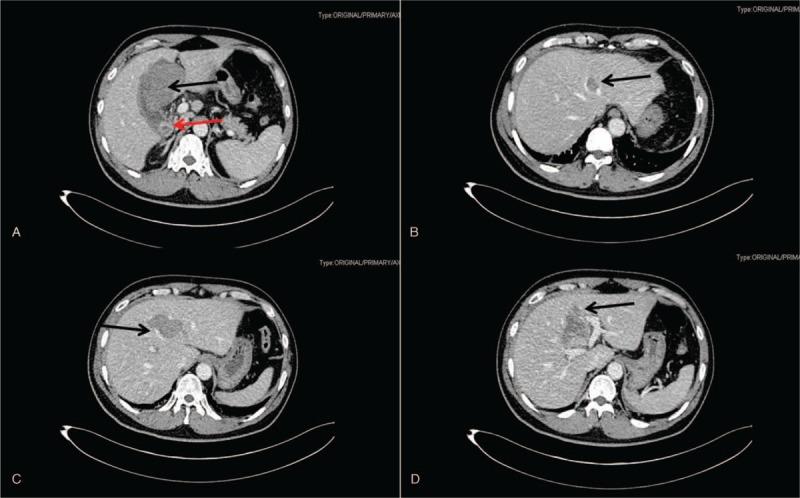

Massive hemoperitoneum and upper gastrointestinal hemorrhage following liver rupture secondary to gallbladder perforation: A case report and literature review.

The patient presented with sudden-onset right upper quadrant pain with tarry stool for 3 days after eating with dysphoria and increasing thirst; gradually, hemorrhagic shock developed. He had no history of trauma, no background of chronic hepatitis, and no cirrhosis.

Hemorrhage secondary to spontaneous rupture of intrahepatic cholangiocarcinoma.

Left hemihepatectomy, cholecystectomy, and common bile duct exploration were performed.

The patient was diagnosed with massive hemoperitoneum accompanying upper gastrointestinal hemorrhage following liver rupture secondary to gallbladder perforation. The postoperative course was uneventful and the patient was discharged after 10 days of hospitalization.